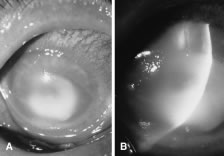

In the early stages of infection, filamentous fungi produce signs that are readily distinguishable from yeast or bacterial keratitis. The most distinctive sign is the presence of delicate, fine, feathery, opalescent, gray-white or yellow-white material in the anterior stroma, surrounded by scant cellular infiltrate or edema (Fig. 1). The epithelium may be intact. The overlying epithelium may be granular and the surface elevated and irregular in contour. Linear infiltrates typically extend into the adjacent stroma. Multiple discrete opacities may develop outside the perimeter of the principal focus of inflammation, either separated by clear stroma or linked by fine linear collections of inflammatory cells and material (Figs. 2 and 3). In the absence of inflammation in the adjacent stroma, branching hyphal fragments may be visualized by biomicroscopy (Figs. 4 and 5). Confocal microscopy may also detect hyphal elements within the stroma.28,29 Peripheral infection resembles noninfectious marginal infiltrative and ulcerative keratitis (Fig. 6). Multifocal keratitis may develop after contact lens wear or injury by multiple projectiles (Fig. 7). In the early stages, iritis is present and the intraocular pressure remains normal. Inappropriate, empirical therapy of fungal keratitis with topical fluoroquinolone or aminoglycoside antibiotics may suppress or eliminate the superficial elements but allow extension of the organisms into the stroma because these agents may possess selective antifungal activity.4,30,31

There is no distinguishing clinical sign by which to recognize the genus or species of the infectious filamentous fungus. F. solani is the most virulent organism and typically produces rapidly progressive infection characterized by epithelial and stromal ulceration, dense stromal necrosis, abundant cellular infiltrate, and edema in the adjacent stroma and hypopyon (Figs. 8 and 9). Delicate feathery components are transient. Individual hyphal fragments are rarely visualized. Infection by certain species of Aspergillus and Scedosporium (Figs. 10 and 11) resembles F. solani keratitis and progresses rapidly. Infection by less virulent organisms, such as Curvularia and Alternaria species, produces small, focal (less than 3-mm diameter) areas of nonnecrotizing stromal inflammation with delicate feathery borders (see Fig. 1 and Fig. 12). Macroscopic pigmentation may develop in keratitis caused by Alternaria, Curvularia, and other dematiaceous fungi (Fig. 13).4,11,14 The central component may progress to dense, opaque, gray-white suppuration in the deep stroma without enlargement in total area and may be accompanied by mild inflammation in the adjacent stroma. Iritis is minimal to moderate. Infection caused by other, relatively less virulent organisms resembles herpes simplex or noninfectious keratitis (Fig. 14).

Candida infection typically produces epithelial ulceration, focal necrotizing stromal inflammation, moderate cellular infiltrate and edema in the adjacent stroma, and mild or moderate iritis in the early stages, indistinguishable from bacterial keratitis (Figs. 15, 16, and 17). Fungal elements cannot be detected by biomicroscopy. If untreated, the keratitis evolves to produce dense suppuration and necrosis of the deep stroma. Although multifocal suppuration may develop in polymicrobial keratitis, there is no distinctive sign of mixed Candida and bacterial infection (Fig. 18).